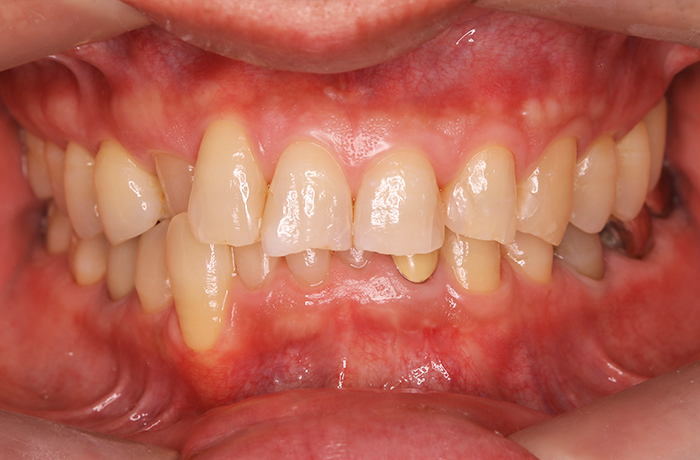

治療後

治療終了後の完成した口腔内と

レントゲン写真

サイナスリフト部の骨再生は良好で、インプラントの安定性も高く、骨吸収や透過像はありませんでした。

最終補綴装着後は咬合バランスが改善し、良好な咀嚼機能が回復。審美性にも優れ、患者様にもご満足いただけました。